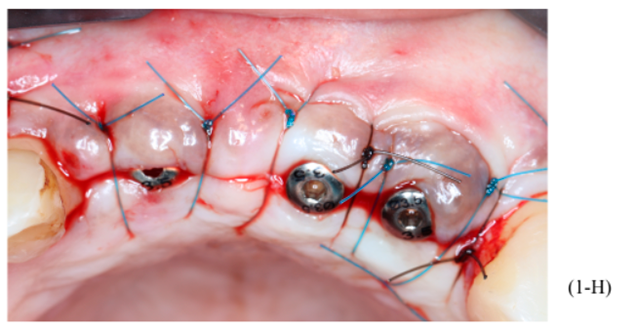

Figuras 3,4,5,6,7 e 8 – Sequência do primeiro ato cirúrgico, onde podemos observar (imagem 3) a incisão do tipo Newmann modificada para ampla visualização do campo operatório e as extrações dentárias. Podemos observar também a descorticalização do processo alveolar e a instalação dos parafusos tipo tenda Implacil De Bortoli de 10 mm, respeitando a distância de pelo menos 2 mm entre cabeças (imagem 4). Foram colocados dois gramas de biomaterial Bio-Oss Geistlich, preenchendo toda cavidade e alvéolos até a delimitação da cabeça dos parafusos (imagens 5 e 6). Antes do fechamento completo da ferida cirúrgica, colocamos membranas de PRF para auxílio na reparação tecidual e proteção do material de enxerto (imagem 7). Para fechamento da ferida cirúrgica, usamos fio do tipo Cytoplast, fornecido pela Implacil De Bortoli. É de extrema importância sua utilização, pois apresenta excelente elasticidade, acompanhando edema cirúrgico pós-operatório, o que diminui o risco de deiscência no pós-operatório.

Foram planejados três implantes do tipo Cone Morse Maestro Implacil De Bortoli 3.5 x 13 mm. Após remoção de maneira facilitada dos parafusos tenda, foram instalados três implantes em ótimo posicionamento tridimensional (imagens 1-E, 1-F, 1-G, 1-H). Todos apresentaram estabilidade primária de 35 Ncm de torque e aguardamos quatro meses para posterior reabilitação protética definitiva com próteses individualizadas de metalocerâmica do tipo parafusada.